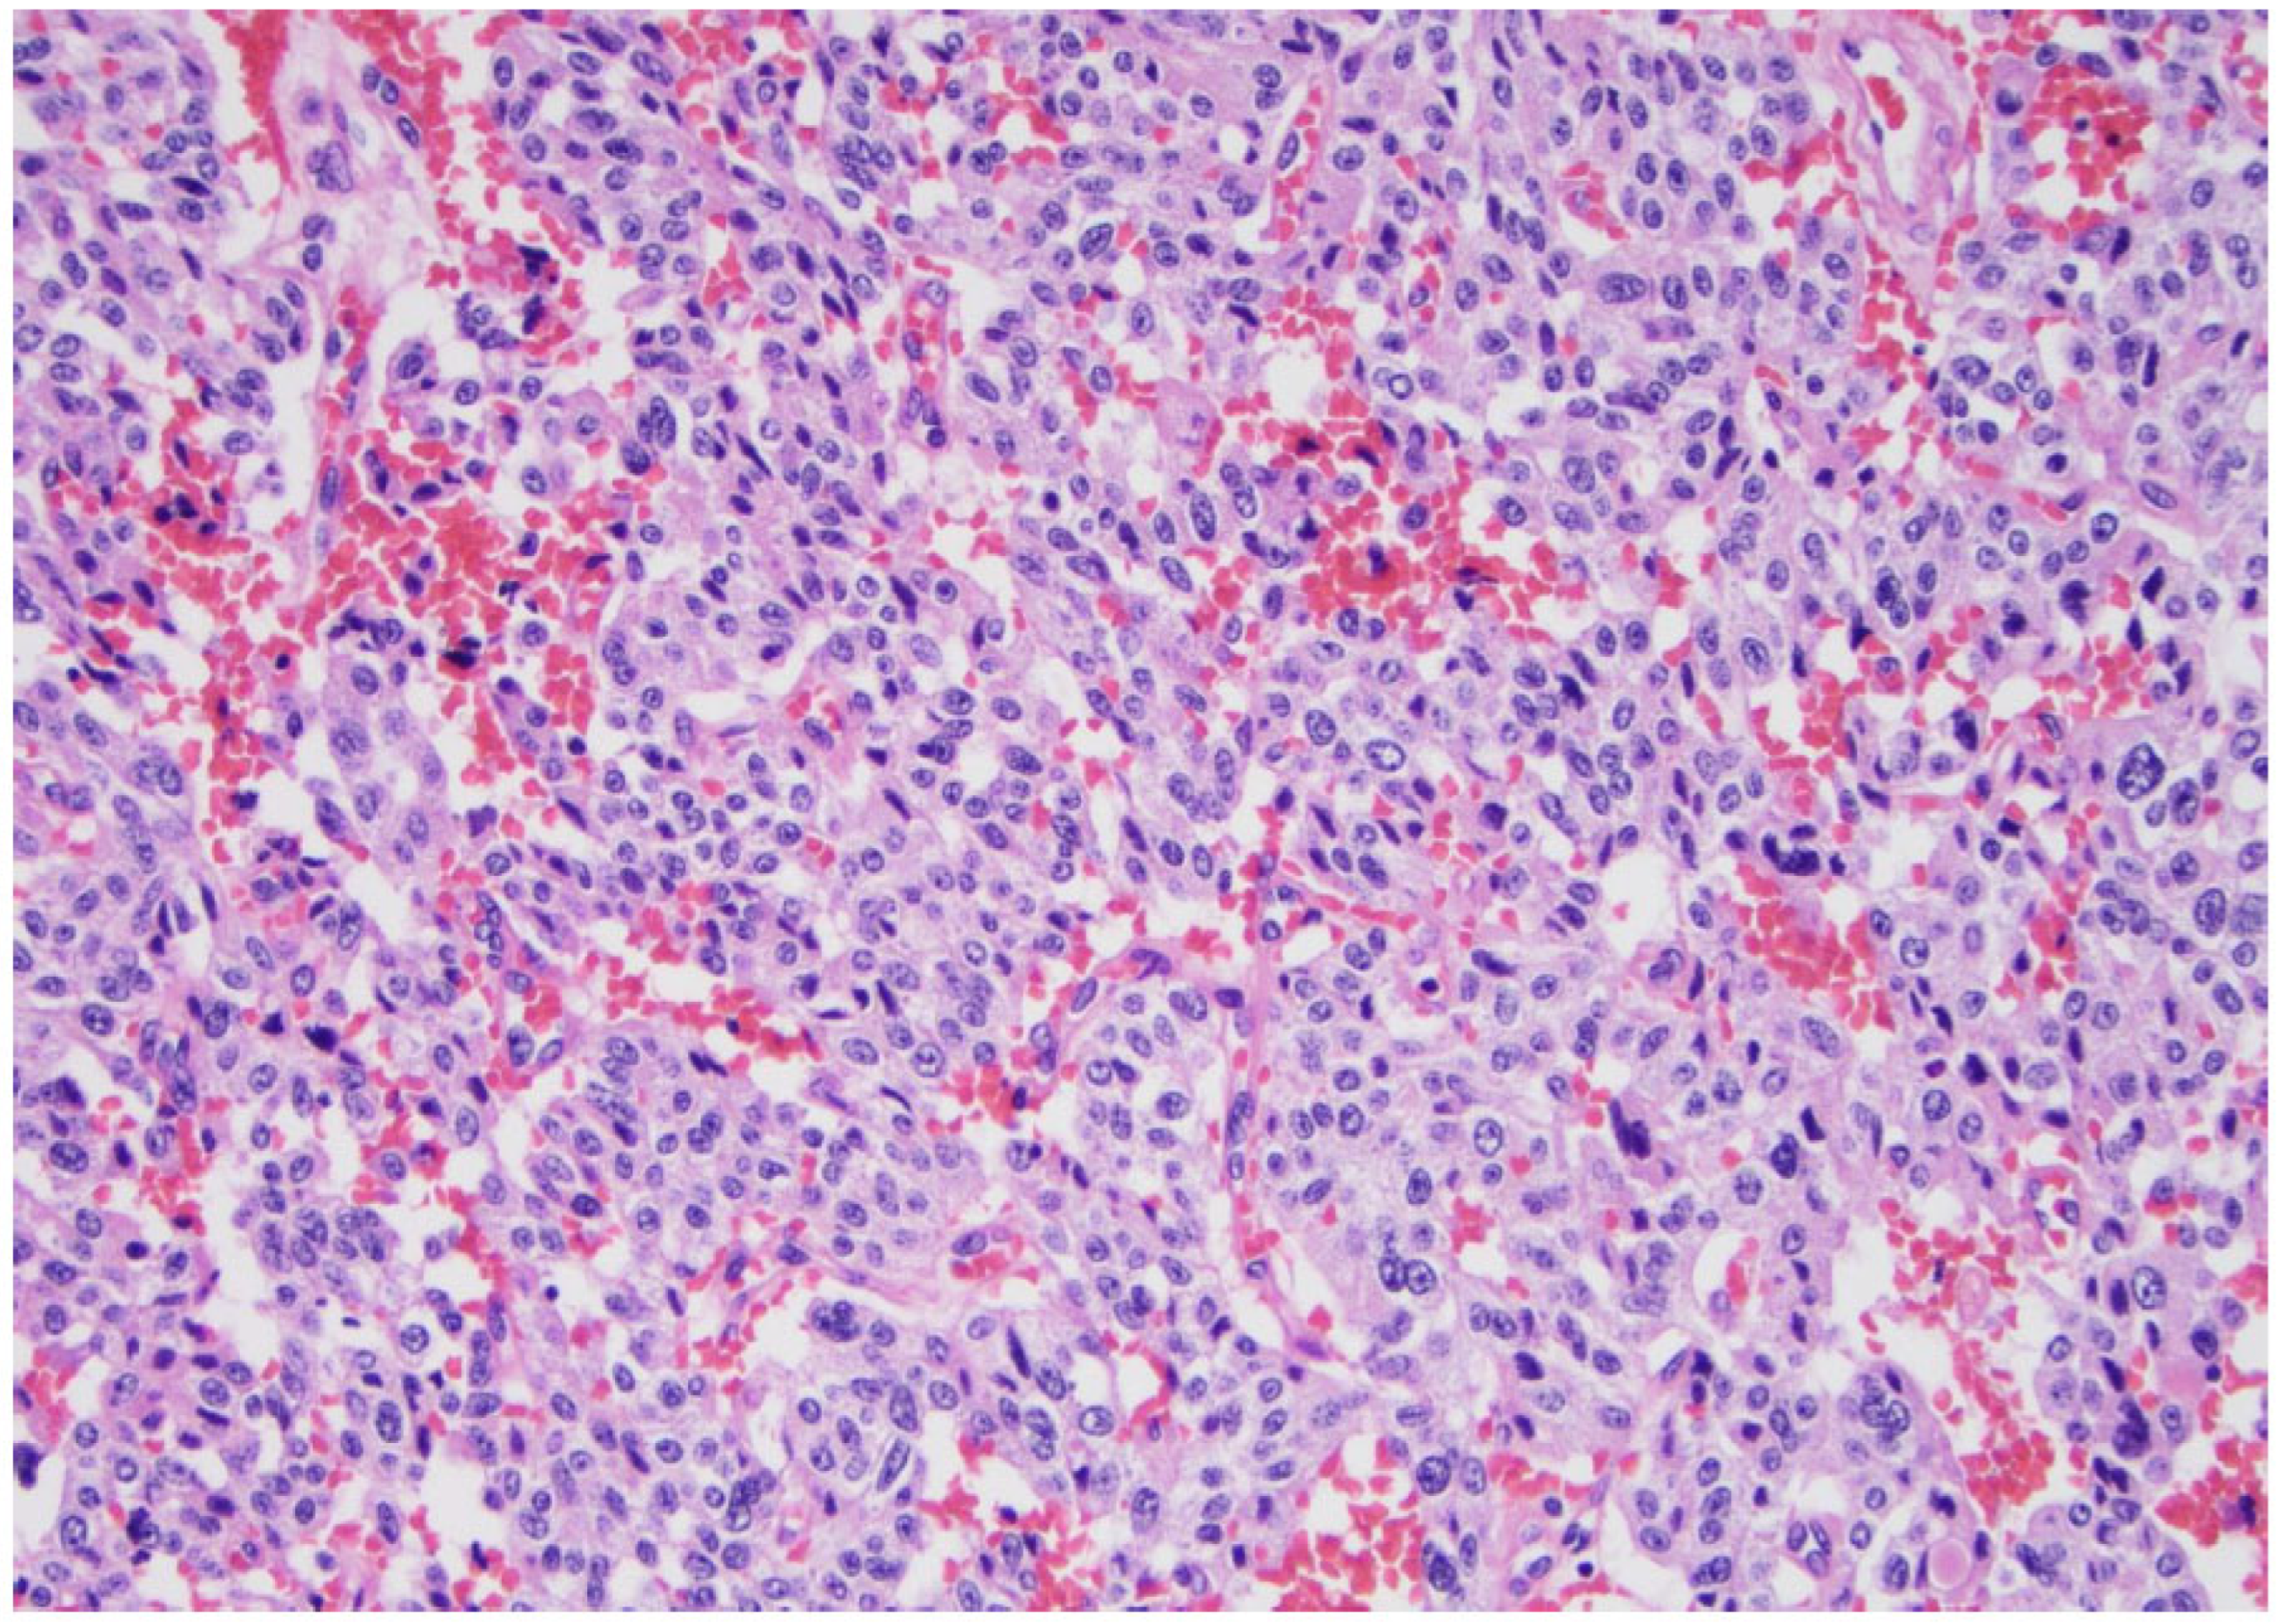

Figure 9. Medullary carcinoma shows lobular or nested groups of medium-sized cells with relatively round or oval uniform nuclei with scattered nuclear variations (×200, H&E stain).

The most significant update for medullary thyroid carcinoma (Figure 9) is the introduction of a grading system called “the International medullary thyroid carcinoma grading scheme”. This is a two-tiered grading system; high-grade cancers are characterized by tumor necrosis; a mitotic count ≥ 5 mitoses per 2 mm2; and/or a Ki 67 proliferation index ≥ 5% (Figure 10 and Figure 11) [10].